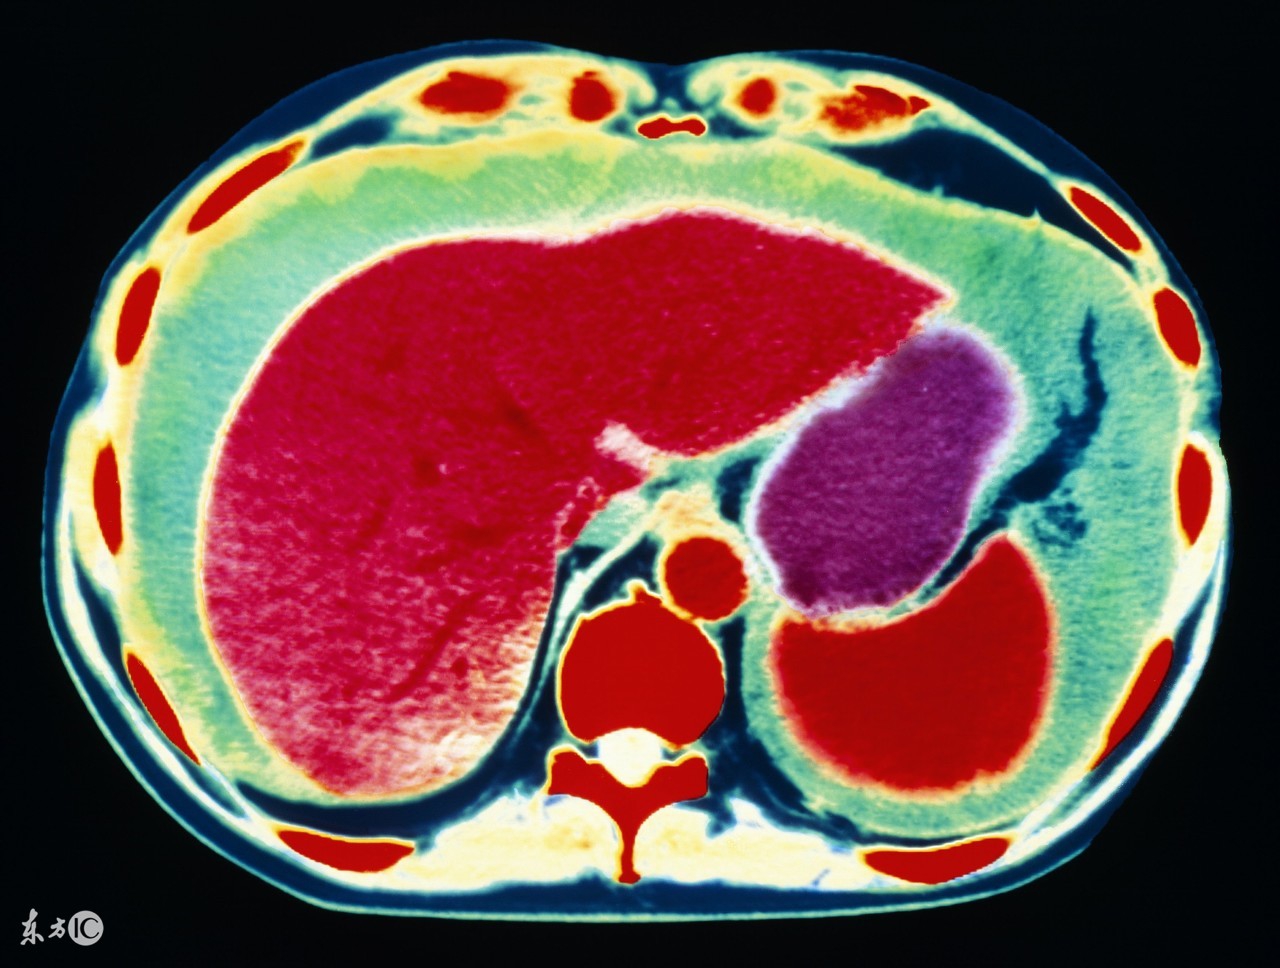

1、肝癌。前面说了,肝病是引起腹水最常见的原因,其中肝癌就是其一。原发性肝癌,发展到一定程度,合并腹水的可能性非常大,其实本质上仍是肝硬化所致,所以肝腹水就是肝硬化腹水。肝硬化时,肝细胞变性、坏死、纤维组织增生,肝内血管床受压、扭曲、变形、狭窄,阻塞了血管,使肝窦淤血,血流量大大降低,门静脉压力升高,同时,毛细血管静脉压力也升高,久而久之,胃肠道、肠系膜、腹膜等血液回流受阻,血管通透性升高,血液中的血浆成分外漏,形成了腹水。肝功能不合,肝脏不能合成白蛋白,低蛋白血症,由于血清白蛋白的降低,血管内胶体渗透压下降,血浆成分外渗而形成腹水。所以,不管什么肝病,到了肝硬化,肝功能不全的阶段,就可能形成腹水。

总结一句话,引起腹水的癌症最常见的是三种癌症:原发性肝癌、胃癌、卵巢癌。其他癌症也可能合并腹水,便相对少见些,所以如果出现大量腹水,而且考虑癌症的话,首先要考虑肝癌、胃癌和卵巢癌,然后考虑其他癌症。但不管什么癌症,都意味着晚期,预后不好,不过,卵巢癌有些例外,即便有腹水,有时也可考虑减瘤性手术,通过手术和化疗等治疗,有相当比例的病人生存时间可达一年以上,不少病人可达两三年甚至更长。